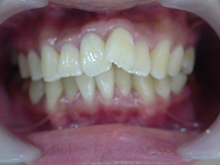

オールセラミックス

金属を使わずに全てセラミックを使用し、光の透過性を上げる事により自然な白い歯に回復させる方法です。

現在では土台から白い材質(ファイバーポストなど)の物を使用することにより、さらに透明感が増し天然歯に近似しています。

オールセラミックは近年進化を遂げており、強度や接着性がかなり改善され、審美的にとても優れたものと成って来ております。

オールセラミックにも色んな種類がありますが、当院ではe-max(二ケイ酸リチウムガラスセラミック、)ジルコニアセラミックスを採用しています。

症 例